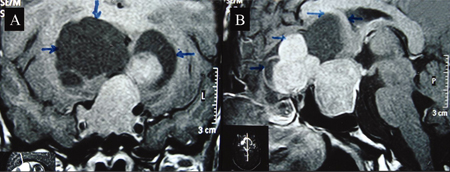

Sellar tumours that are extremely rare.[Figure caption and citation for the preceding image starts]: Coronal (A) and sagittal (B) post-contrast magnetic resonance image T1 weighted sections showing a large intrasellar tumour with suprasellar component. Suprasellar solid component shows a lobulated margin with peripheral non-enhancing cystic areas (margins shown by arrows), which are mildly hyperintense compared with cerebrospinal fluid in basal cisternsBMJ Case Reports 2009; doi:10.1136/bcr.01.2009.1483 [Citation ends].